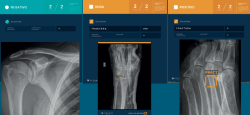

En nuestro caso, decidimos que toda radiografía que llega al PACS se enviara directamente y de manera automática al análisis por la IA, evitando un uso “a demanda” del médico, para favorecer su consulta. El resultado del análisis es devuelto al PACS en un plazo de 1-2 minutos, poniéndolo a disposición del personal médico para su valoración. Los resultados se presentan de manera clara y fácil de interpretar, en 3 niveles: negativo, dudoso o positivo (Figura 2); los dos últimos señalan con un recuadro en la radiografía la imagen de fractura. La diferencia entre un resultado positivo (recuadro con línea continua) y uno dudoso (recuadro con línea discontinua) estriba en un nivel de confianza alto o intermedio para la lesión detectada. Esta solución de IA detecta fracturas en todas las localizaciones anatómicas excepto el cráneo y la columna cervical, y, además, identifica derrames articulares, luxaciones y lesiones óseas. Como control de calidad, se indica el número de imágenes recibidas y el número de imágenes analizadas.

retla.08115.fs2402001-figura2.png

Figura 2. Resultados de la valoración de la inteligencia artificial (IA), tal y como aparecen en el PACS (picture archiving and communication system): positivo, duda y negativo. Los resultados dudosos y positivos aparecen resaltados en naranja y con las zonas de interés señaladas con un recuadro. También se especifica si la lesión detectada es una fractura, derrame, luxación o lesión ósea.

Figura 2. Resultados de la valoración de la inteligencia artificial (IA), tal y como aparecen en el PACS (picture archiving and communication system): positivo, duda y negativo. Los resultados dudosos y positivos aparecen resaltados en naranja y con las zonas de interés señaladas con un recuadro. También se especifica si la lesión detectada es una fractura, derrame, luxación o lesión ósea.